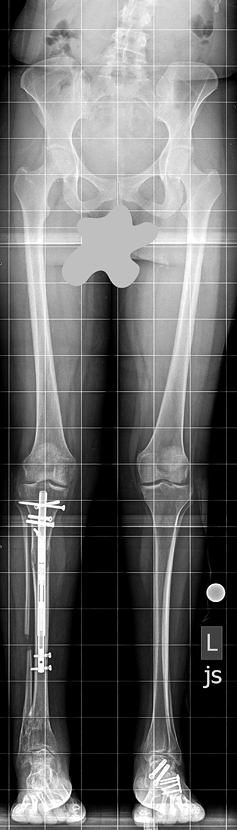

Lisa came to the International Center for Limb Lengthening (ICLL) having already had a dozen surgeries elsewhere to address her bilateral clubfeet. She went to several hospitals looking for help for her painful arthritic ankles and was often given the suggestion of having a total ankle fusion. She shares that she even wondered if she would possibly have to amputate her feet in the future. When Lisa was told it would be helpful to fix her limb length discrepancy before further addressing her feet, she was referred to the ICLL. Dr. Herzenberg recommended that she lengthen her shorter leg with the Precice internal lengthening system.

“Once I knew I could legitimately make myself even, all I could feel was excitement. I would tell anybody looking into this to prepare for a longer recovery than originally planned, especially if you are a woman beyond your twenties.” In addition to keeping expectations for bone healing rates flexible, she suggests patients “over-plan” all the logistics and use high quality supplements to support bone and tissue growth. “Plan for the growth pain and the hard work of physical therapy,” she warns, “but be excited at the prospect of standing even. I was finally even after 20 years of asymmetry.”

Lisa adds, “The entire process has been difficult, probably because I had arthritis in both ankles and they increased significantly in pain post the pin surgery…. Regardless, there has been vast improvement in the way I walk and just the way I stand. It has been an arduous learning process, because all my functioning had to respond to the realignment of my body. But a year and a half after surgery, I have seen the benefits, have come a long ways, and expect to go further.”

“Good has already come of it, because I now have the AFO [Ankle Foot Orthotics], Fabtech Braces, which protect my arthritic ankles, but assist me to be more athletic. These orthotics are likely better because my legs are even…. In the long run, the limb lengthening accomplished what it was supposed to, and I am very glad I did it, and I know my hips are already thanking me. Someday as I decide what to do with my feet, I think it will be more successful because my legs are now even.”